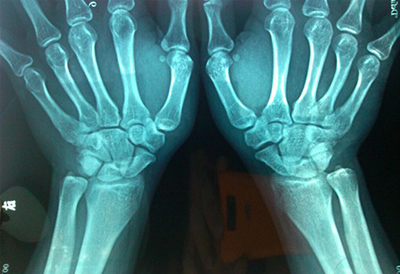

骨密度正常值全名是人体骨骼矿物相对密度,是人体骨骼抗压强度的一个关键指标值,以克/每立方厘米表达,是一个绝对值。

身体骨矿物含水量与人体骨骼抗压强度和细胞外液平稳息息相关,因而是点评人们身体状况的关键指标值。在生理学情况下,肌肉骨骼中骨矿物含水量随年纪不一样而异,在病理学情况下,一些药品可造成骨矿物含水量更改。因此人体骨骼矿含量的定量测定已成为现代医学的一个重要课题。

骨矿的基本检验关键是根据对身体骨矿含水量测量,立即得到骨矿物关键是钙的精确含水量,它对分辨和科学研究人体骨骼生理学、病理学与人的衰退水平及其确诊满身各种各样病症均有关键功效。平常人骨矿含水量与性別、年纪息息相关。同龄不同性别有差异,女性低于男性。同一性別年纪提高产生相对的转变,35-40岁之后骨矿含水量出現慢慢降低发展趋势,女士尤其明显。

超声骨密度检测仪品牌分析这些生理变化数据也为诊断不同原因引起的疾病和骨矿物质含量变化提供了重要的诊断依据。